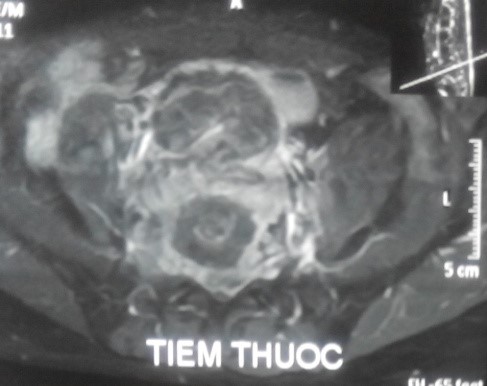

Trên X-quang, CT scanner khối u phá hủy vỏ xương gần hết thân và cuống sống L5.

Trên MRI, khối u giảm tín hiệu xâm lấn nhiều ra phía trước vào tiểu khung, xâm lấn ra phía sau chèn ép vào ống sống. Khối u ngấm thuốc mạnh, tăng sinh mạch nhiều trên phim MRI có tiêm thuốc.

CT scanner và MRI giúp đánh giá vỏ xương, tổn thương hủy xương cũng như mức độ thâm nhiễm quanh u. Trên T1W, T2W khối u TBKL đồng tín hiệu với tổ chức cơ, có thể giảm tín hiệu do collagen và hemosiderin, T1W sau tiêm ngấm thuốc. Phần mềm quanh u có thể hoại tử nhiễm trùng, đặc điểm này thường không gặp trong nang xương phình mạch, có thể để chẩn đoán phân biệt [5,11,12]. Bệnh nhân của chúng tôi, khối u phá vỡ thân đốt L5, thâm nhiễm phầm mềm rộng chèn ép ống sống phía sau, khối u cũng thâm nhiễm rộng ra phần mềm phía trước vào tiểu khung kích thước lớn khoảng 10 x 10cm, khối u đẩy lồi và một phần ôm lấy ngã ba chủ chậu ra phía trước gây khó khăn cho việc phẫu thuật lấy bỏ khối u và là yếu tố tiên lượng tái phát cao sau mổ.